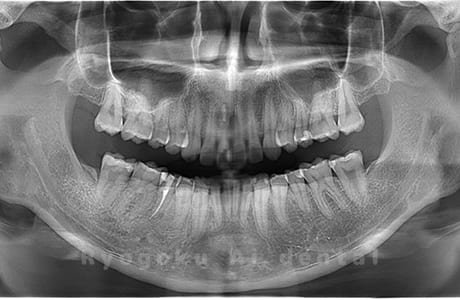

Case03

-

- 原因

- 上顎、下顎の親知らず

- 治療内容

- 上下4本の親知らずを抜歯したケースです。

<リスク・副作用>

手術後は痛み、腫れ、痺れなどの副作用が生じる場合があります。